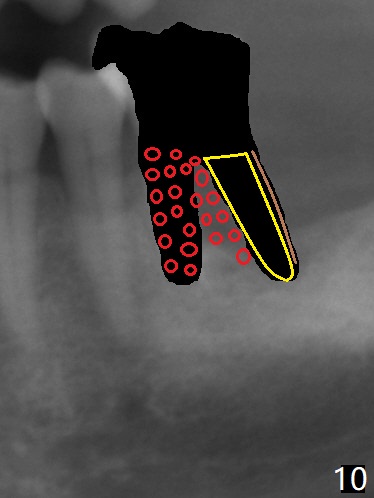

After tooth extraction (Fig.4), a medium-sized implant (4.5 mm, Fig.5 green) will be placed in the mesial socket, but the coronal end of the long axis of the implant (white line) will be in the middle of the socket for future restoration. The gingival margin of the socket is also uneven (Fig.6 pink). Before placement of the final abutment (Fig.7 blue), pack allograft (red circles) over the exposed implant surface until the platform of the implant. After placement of Osteogen plug in the distal socket (Fig.8 yellow), more of allograft is placed coronally. An immediate provisional (Fig.9 white) is to be fabricated to keep the graft in place. If the socket is deemed to be unsuitable for immediate implant, place PRF membrane(s) distoocclusally (Fig.10 purple), followed by collagen membrane and suturing.